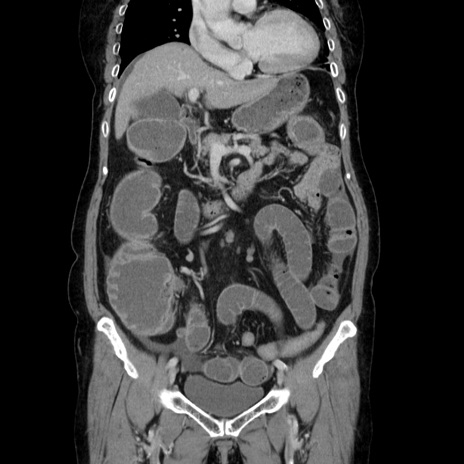

症例5(冠状断像)

【症例】70歳代女性

【主訴】お腹が張る

【現病歴】1週間くらい前から腹部膨満の自覚あり。昨日夜から増悪したため、本日救急外来受診。

【身体所見】意識清明、BT 36.5℃、BP 165/106mmHg、HR 80bpm、SpO2 98%、腹部:膨満、軟、自発痛・圧痛なし、触診にて不快感あり、腸蠕動音:減弱

【データ】WBC 12600、CRP 1.04

横断像